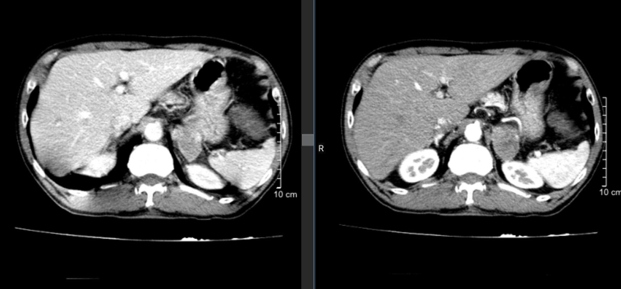

- CT bụng:

- Hình 3: Hình ảnh cắt lớp vi tính ổ bụng cho thấy có khối ngấm thuốc tuyến thượng thận trái kích thước 44x30mm - theo dõi thứ phát.